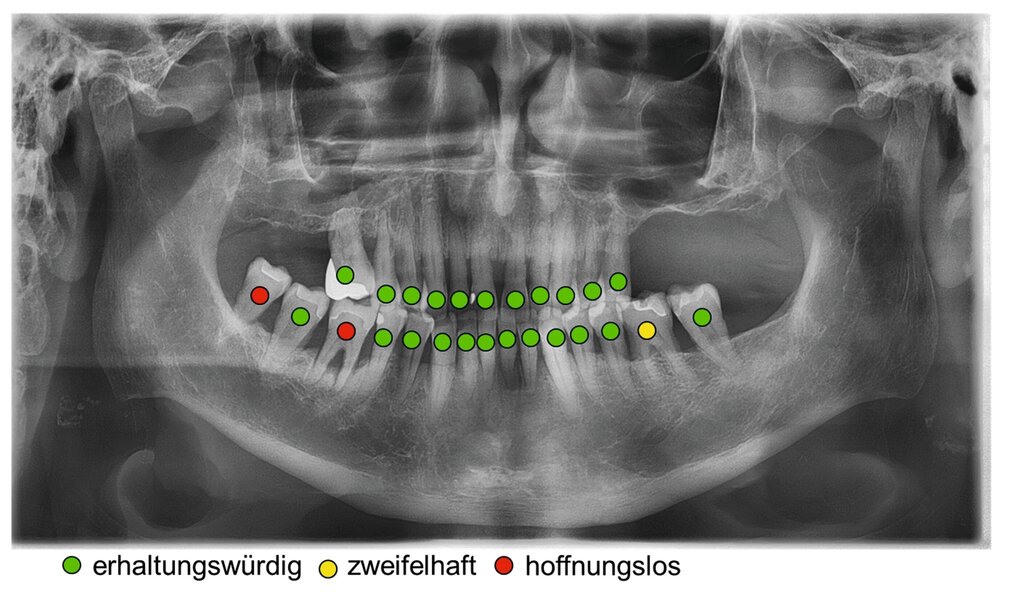

Dennoch geben Prognosesysteme, insbesondere bei komplexen Situationen, eine Hilfestellung bei der Entscheidung über den Zahnerhalt. Jedoch sollte man diese zu unterschiedlichen Zeitpunkten innerhalb der Parodontitistherapie erneut durchführen und sich wiederholt die Frage stellen, ob durch die derzeitige Therapie eine parodontale Stabilität des Zahnes erreicht werden kann [Kwok und Caton, 2007]. Die Abbildungen 5 bis 8 stellen diese Situation bei einem 56-jährigen Patienten mit Parodontitis dar, bei dem sich die zahnbezogenen Prognosen nach drei Jahren Parodontitistherapie deutlich verbessert haben.